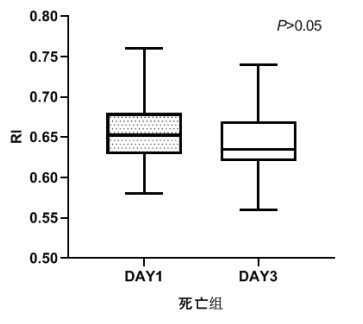

TCD参数组内治疗前后比较,生存组中无论PI还是RI在第3天时均较第1天有了明显下降,具有统计学意义(P < 0.05), 见图 2和图 3。死亡组在第1天和第3天测得的PI和RI值比较差异无统计学意义(P > 0.05),见图 4和图 5。可见生存组经治疗后脑循环较前改善,而死亡组治疗前后脑循环无明显改变。

| 图 5 死亡组第1天和第3天RI比较 Fig 5 Comparison of RI between the first day and the third day in the death group |

|